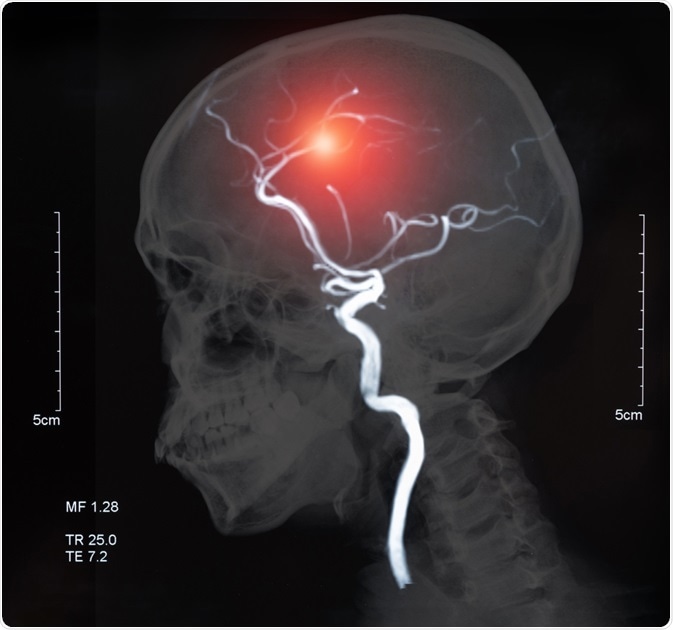

Image Credit: create jobs 51/Shutterstock.com

Diagnosis of the different types of cerebrovascular disease can be made through different neuroimaging tests. Cerebral angiography is used to visualize the arteries of the head and neck, which are not normally seen using an x-ray.